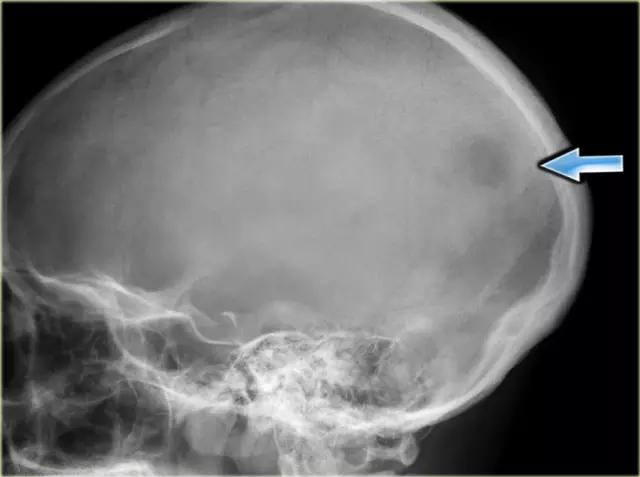

上图EG在颅骨中的典型表现为边界欠清的溶骨性病变。